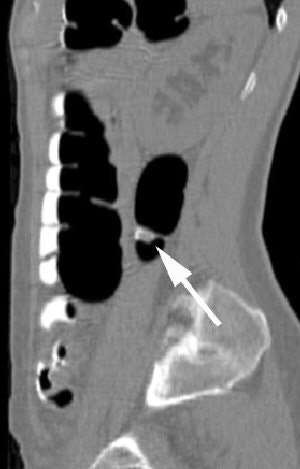

| Coronal VC image confirms the presence of the polyp (arrow) within descending colon. Image courtesy of Dr. Riccardo Iannaccone. |

As for study limitations, the cohort remains relatively small, and the observers "have vast experience using primary 2D," Iannaccone said. Readers with less experience might have different results.

"CTC without cathartic preparation compares favorably with colonoscopy for detection of polyps 8 mm in diameter or larger, even in asymptomatic patients at average risk for colorectal cancer," Iannaccone concluded. "But certainly a larger cohort must be studied in order to confirm such promising results."